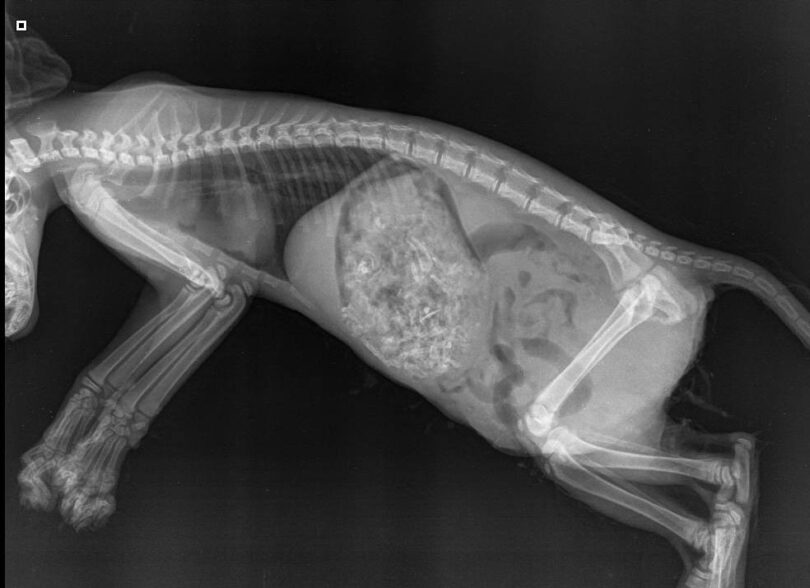

Vsebina poročila obdukcije nam ni točno znana, po besedah veterinarskega inšpektorja Marka Bekeša, ki obravnava ta primer, pa sklepamo, da poškodbe, ki so mački povzročili otroci, verjetno niso bile usodne. Kar pa seveda ne pomeni, da se to kljub temu ne definira kot hudo mučenje živali.